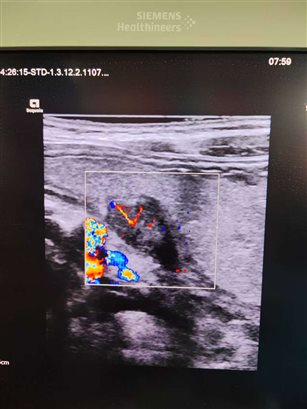

患儿男性,6岁,因阵发性腹部疼痛来诊。患儿口服300毫升胃肠超声造影剂后,于胃窦部小弯侧发现一实性团块,病变起自于黏膜下层,累及固有肌层。超声诊断考虑异位胰腺。

1. 形态与大小:多为圆形、椭圆形的实性结节,大小一般在数毫米到数厘米不等,边界相对清晰。

2. 内部回声:回声强度和正常胰腺组织类似,多为中等回声,分布比较均匀;如果异位胰腺组织内出现囊性变、钙化或脂肪浸润,回声会变得不均匀。

3. 特征性表现:部分病灶可出现 “导管征”,即超声下能看到一个细小的无回声管状结构,这是异位胰腺内的胰管,是相对有辨识度的征象。

与周围组织的关系:病灶通常紧贴消化道黏膜层或黏膜下层,和周围组织没有明显粘连,加压超声探头时,结节形态变化不明显。